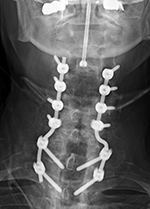

A battery pack overlies the right 12th rib. Wires are going to the bilateral bony fusion masses. There is a laminectomy from L2 to L5 with bilateral pedicle screws and a pedicle plate on the right and a connecting rod on the left. Brantigan vertebral cages are at the L5-S1 disk space. From Hunter, 2004 |